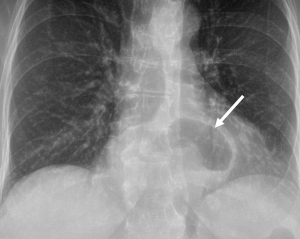

The main components of a diagnostic work-up and characterization of PEHs are a contrast swallow study and EGD. Chest X-rays may reveal a lucency in the retrocardiac space indicative of herniated stomach (see Figure 1) or pneumonia indicative of aspiration and these abnormalities are often the first clue to diagnosis. A chest X-ray alone, however, is not typically adequate in the work-up, as the differential diagnosis includes a mediastinal cyst, abscess, dilated/obstructed esophagus or other type of diaphragmatic hernia. CT scans of the chest and abdomen are helpful to understand the extent of herniation, accurately measure crural separation, and may be important in the acute setting. However, they are not always necessary in the elective setting, with contrast swallow studies and EGD being commonly used (12). Contrast swallow studies help classify the type of hernia by delineating the location of the GE junction and showing the extent of herniated stomach (see Figure 2). They can also help identify functional abnormalities of the esophagus, such as poor peristalsis or tertiary contractions, and may reveal reflux (either spontaneous or provoked).